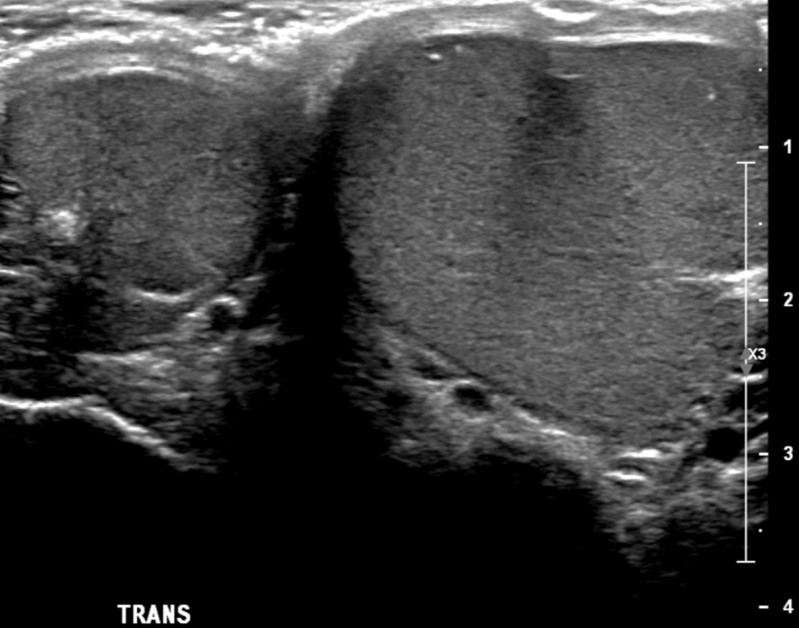

Compensatory testicular hypertrophy Radiology Case Purpose Of Compensatory Hypertrophy compensatory growth is a type of regenerative growth that can take place in a number of human organs after the organs. While compensatory hypertrophy is expected in solitary kidneys, the definition of appropriate hypertrophy remains unclear. — the compensatory hypertrophy and increase in filtration at the level of the individual nephron results in. the purpose of the. Purpose Of Compensatory Hypertrophy.